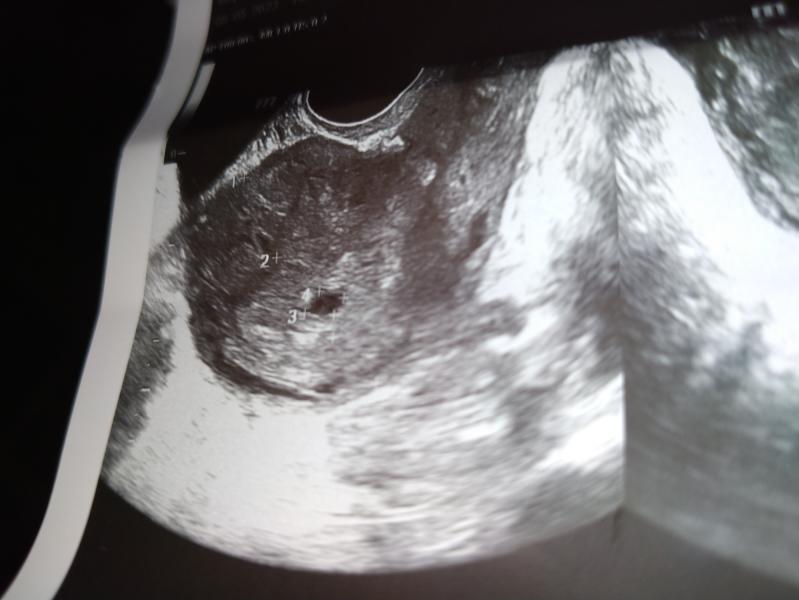

Девочки, срок по узи 6,1 нед(по узи плодное яйцо на 5 недель) Матка по УЗИ увеличена на 8 нед.

Узистка предположила , что два ЖЕЛТОЧНЫХ МЕШКА. А вы что-нибудь видите?